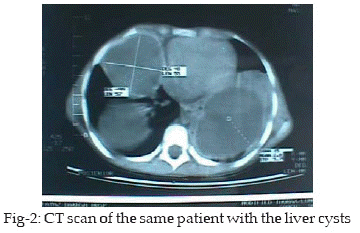

In one case that had bilateral lung cysts (Fig-1, 2), Right thoracotomy was followed by left thoracotomy in three months. All 36-lung cysts during thoracotomy underwent drainage of cyst, removal of germinative layer, repair of air-leak and finally obliteration of cavity by capitonage. Out of 34 liver hydatid cyst 28 underwent omentoplalsty while the remaining 6 were managed by external drainage due to huge cyst, small and inappropriate omentum or difficult cyst location behind the liver. In the remaining 6 cases who had hydatid cyst in other organs 3 in spleen, two in omentum and one in pelvis, all were operated on splenectomy, omentectomy and removal of cyst respectively. We did not find any serious postoperative complication, including chronic air-leak in thoracotomy cases or bile-leak in liver cases. But postoperative atelectasis was common which were treated by chest physiotherapy and in some cases with bronchoscopy by lavage, suction of airway secretions and mucus plaques. We had no mortality. All patients were given albendazol 20mg/kg orally daily for at least three months. All patients were followed by abdominal ultrasonography and chest- x-Ray every three months. No cyst recurrence or major chronic complication was noted during 48 months follow up. We did not use any scolicidal agent in our operations. We carefully isolated cyst during surgery to prevent possible leaks, by drainage or intact removal of cyst.